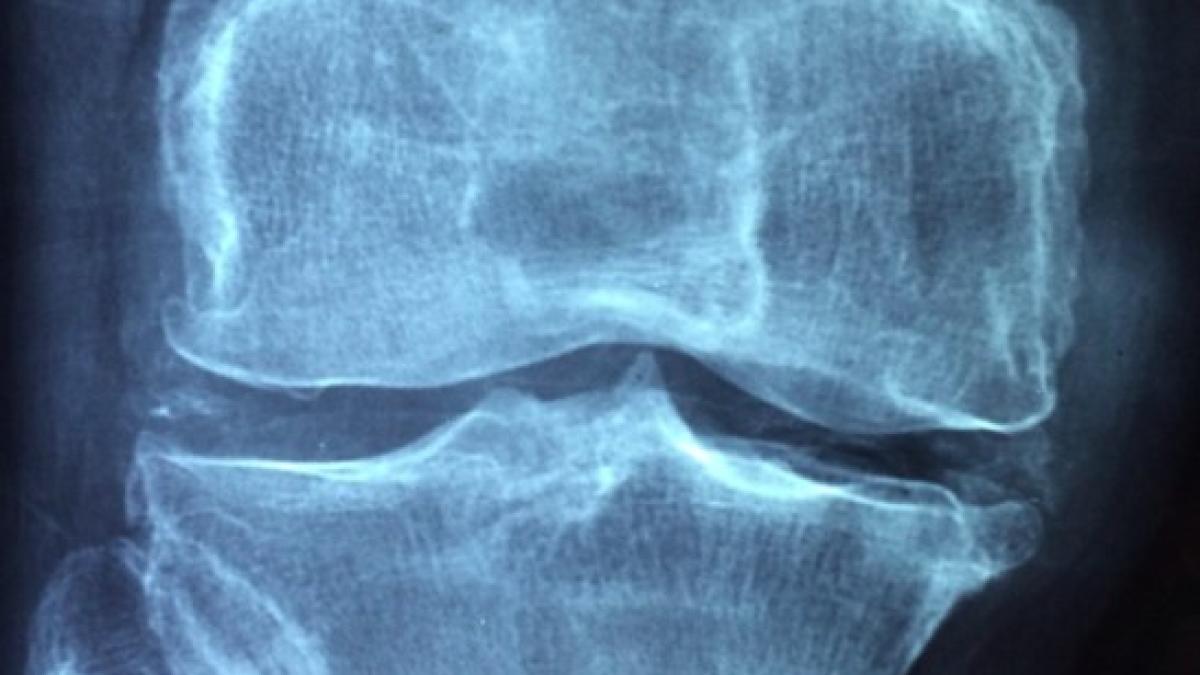

Un medicament folosit în tratarea artritei va fi utilizat în cadrul unui studiu chinez.

Un medicament folosit în tratarea artritei va fi utilizat în cadrul unui studiu chinez referitor la vindecarea pacienților infectați cu noul coronavirus COVID-19, a transmis Comisia Națională de Sănătate de la Beijing, conform Mediafax.

Medicamentul numit Actemra, produs de Roche, ar putea avea efecte pozitive în cazul pacienților care au plămânii puternic afectați de virusul COVID-19, prin reducerea inflamației.